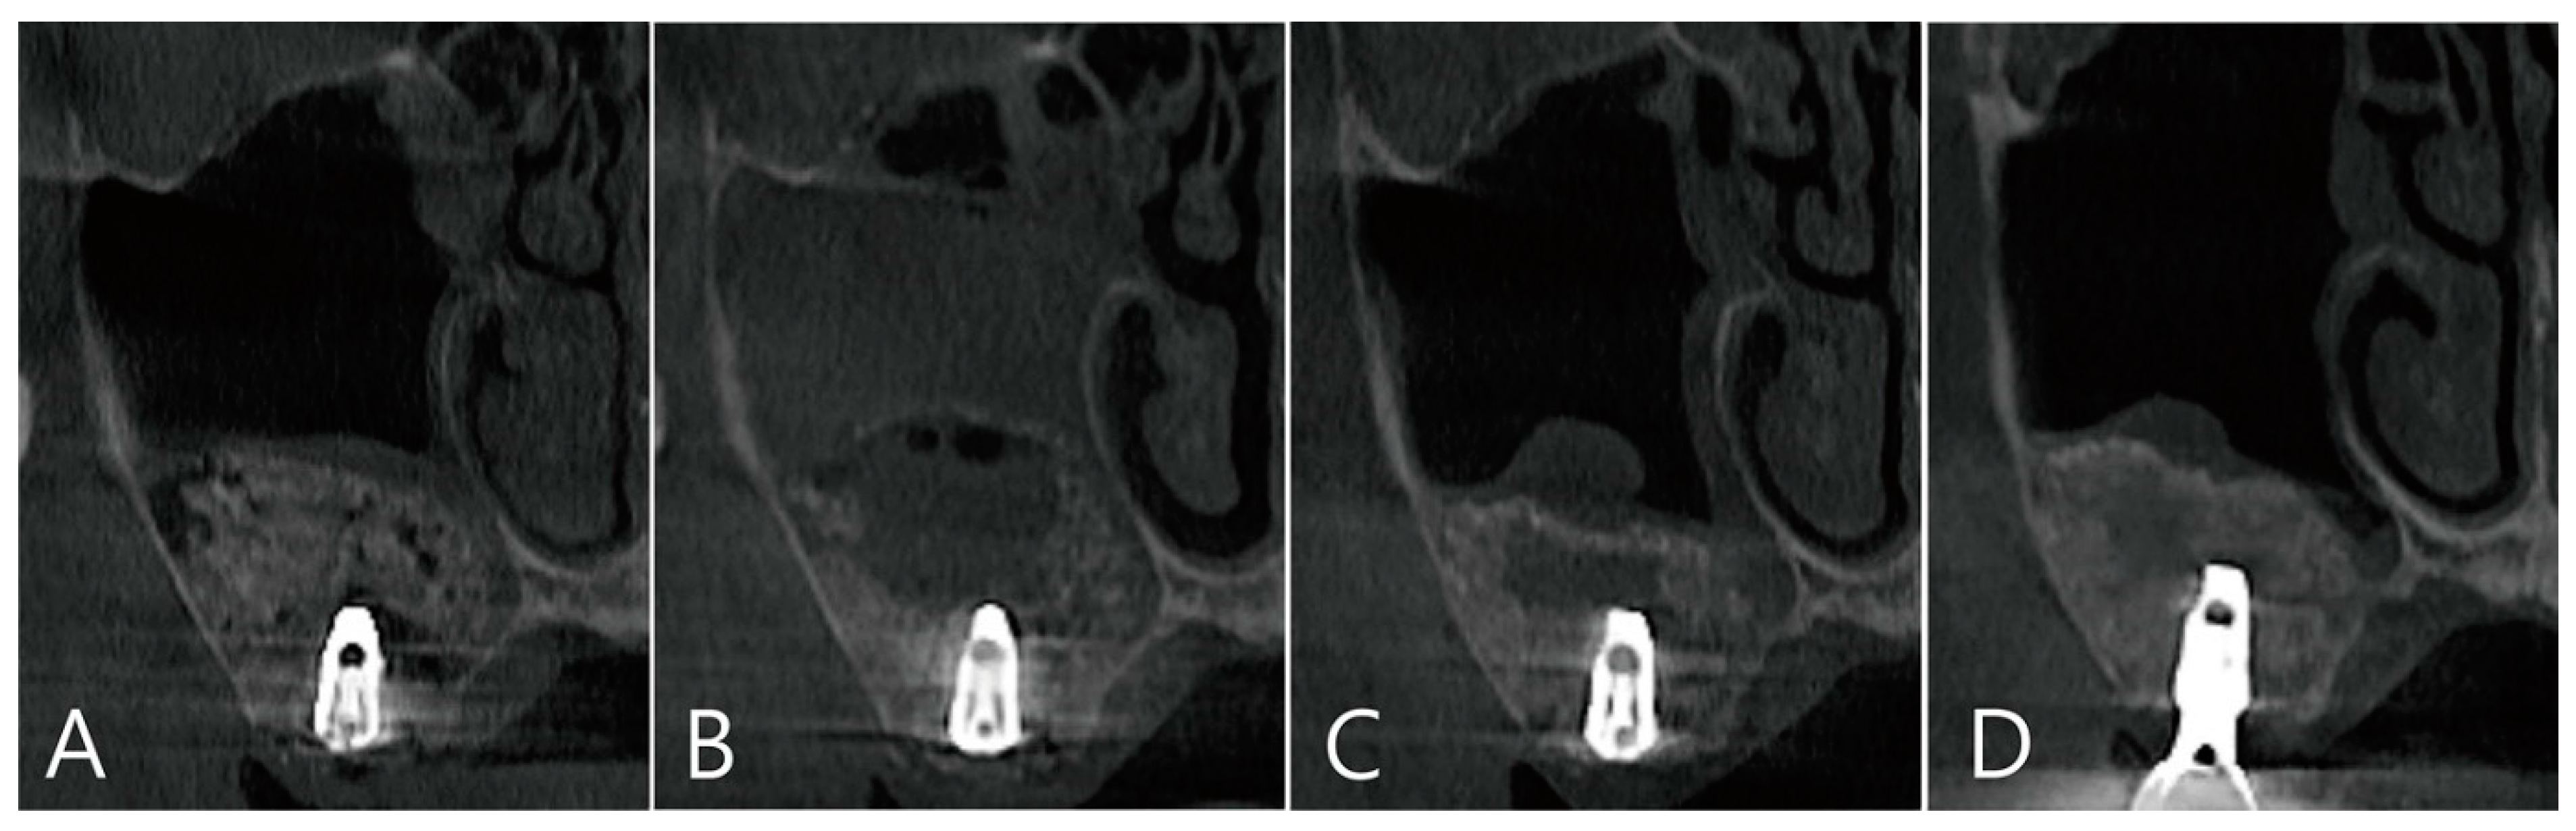

The coronal image of the CBCT scanned at the #27 implant site was examined. In the image taken immediately after surgery there was no leakage of bone graft particles (Figure 13A), however, a very large grafting void appeared in the image taken one week after surgery (Figure 13B). This grafting void showed a cystic appearance at the implant apex, although its size was reduced on CBCT taken after six months (Figure 13C). On the CBCT taken two years after the grafting void was removed, the grafting void was replaced with new bone (Figure 13D).

Figure 13. The coronal image of the CBCT scanned at the #27 implant site was examined: (A) in the image taken immediately after surgery, there was no leakage of bone graft particles; (B) however, a very large grafting void appeared in the image taken one week after surgery; (C) this grafting void showed a cystic appearance in the implant apex, although its size was reduced on CBCT taken after 6 months; (D) in CBCT taken 2 years after the grafting void was removed, the grafting void was replaced with new bone.